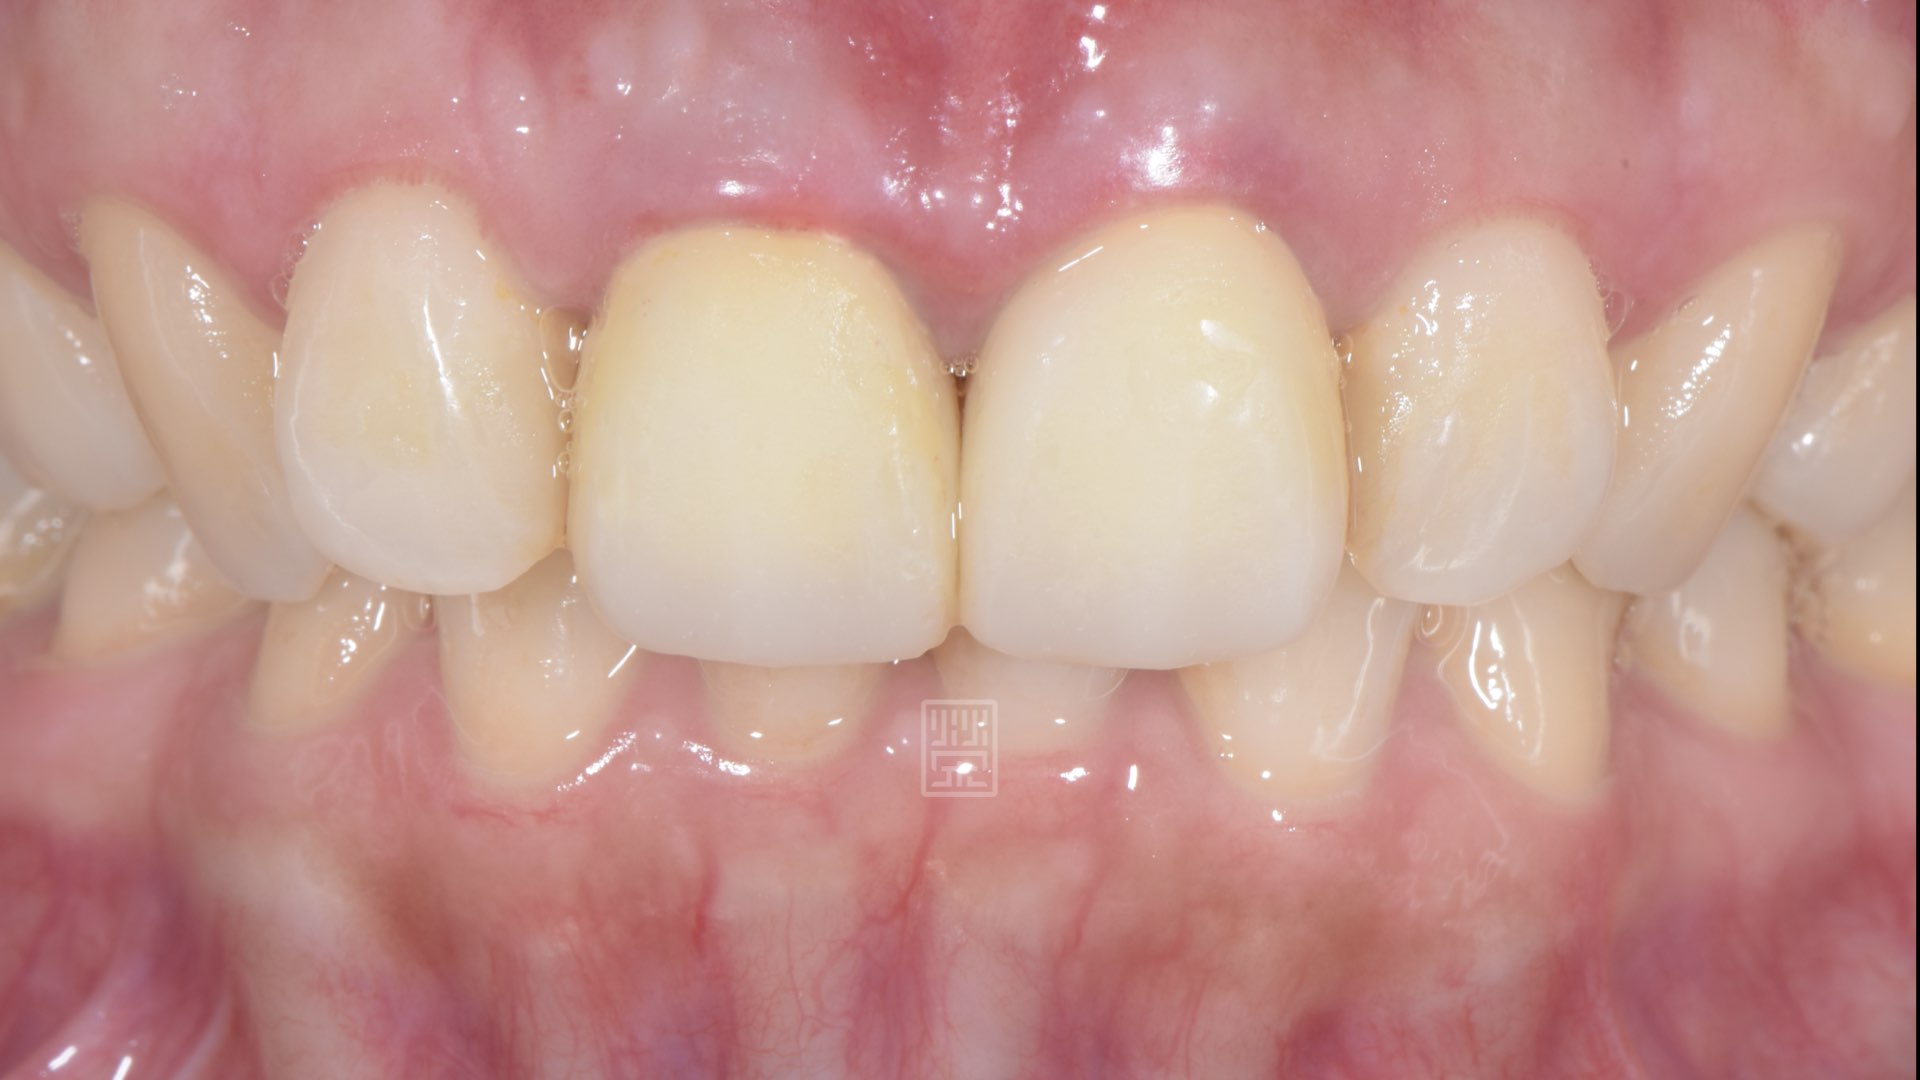

六週後牙齦穩定